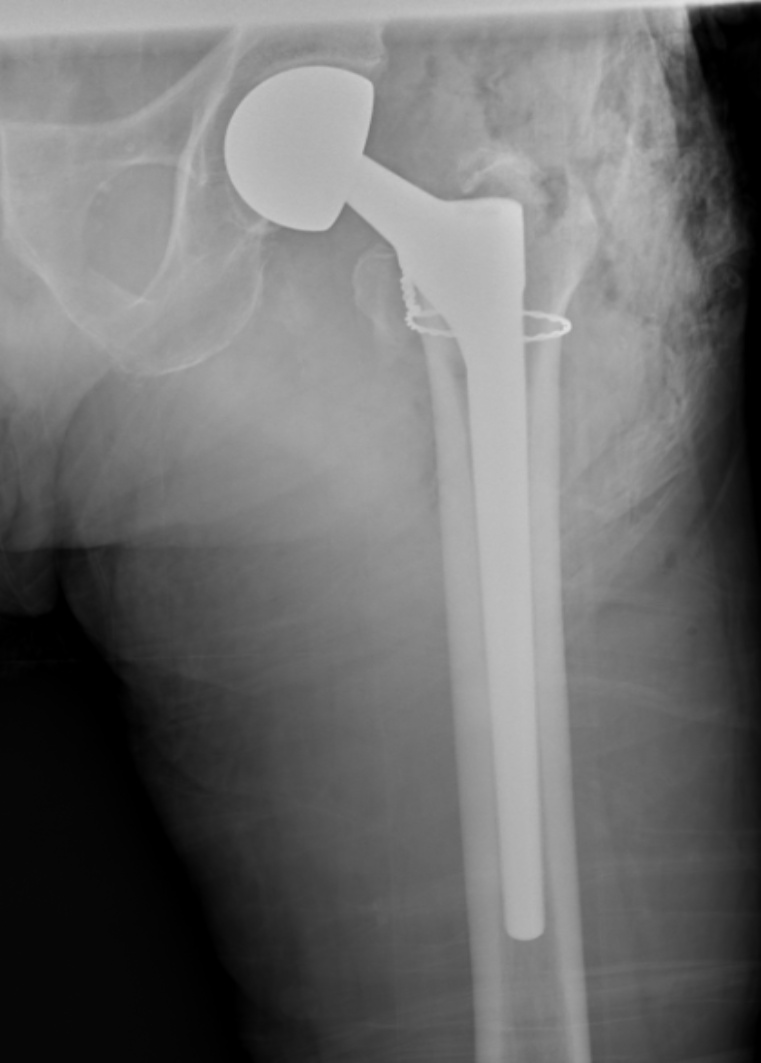

典型病例影像学表现见图1~10。图1为86岁女性右侧股骨转子间骨折(Evans Ⅲ型)患者,术前X线示骨折断端部分错位,术后X线示骨折位置可以及假体位置良好;图2显示了一名81岁男性患者,诊断为左侧股骨转子间骨折,类型为Evans V型,合并股骨干陈旧性骨折。患者接受了生物型加长柄半髋关节置换手术,并进行了股骨近端的钢丝捆扎内固定。术后X线示假体位置良好,股骨近端予钢丝捆扎固定;图3为87岁女性左侧股骨转子间骨折(Evans V型)患者,术后X线示假体位置良好,股骨大小转子骨折位置可,钢丝捆扎固定在位有效;图4为75岁女性左侧股骨转子间骨折(Evans V型)患者,术前X线示左侧股骨转子间骨折PFNA术后、骨折未愈合、内固定断裂。术后假体匹配良好,股骨近端钢丝内固定稳定可靠;图5为75岁男性左侧股骨转子间骨折(Evans IV型)患者,术后股骨大转子出现轻度位移,假体位置正常。图6为87岁男性左侧股骨转子间骨折(Evans V型)患者,给予DAA入路加长柄半髋关节置换,术前X线片,清晰地显示出左侧股骨转子间的骨折情况,术后X线影像,显示股骨的大小转子骨折位置良好,钢丝内固定装置在位稳定,假体位置良好;图7为77岁女性右侧股骨转子间骨折(Evans V型)患者,术前X线片显示右侧股骨转子间存在骨折且股骨大小转子均有累及和移位,术后X线片显示股骨小转子轻度移位,内固定装置位置稳定,假体位置良好;图8为70岁男性左侧股骨转子间骨折(Evans III型)患者,术前的X线片,清晰地显示了左侧股骨转子间的骨折情况,股骨近端髓腔钙化灶,术后假体位置满意;图9为77岁女性右侧股骨转子间骨折(Evans V型)患者,术前X线片,显示右侧股骨转子间及转子下部位骨折情况。术后假体匹配良好;图10为71岁男性右侧股骨颈骨折(Evans IV型)患者,术前X线片,显示右股骨转子间骨折的情况;术后X线表明股骨的大转子和小转子骨折位置保持良好,内固定装置稳固,术后假体位置正常。

Figure 1. 86-year-old female patient with right intertrochanteric fracture of femur (Evans type III). (a) Before surgery; (b) After surgery

1. 86岁女性右侧股骨转子间骨折(Evans Ⅲ型)患者。(a) 术前;(b) 术后